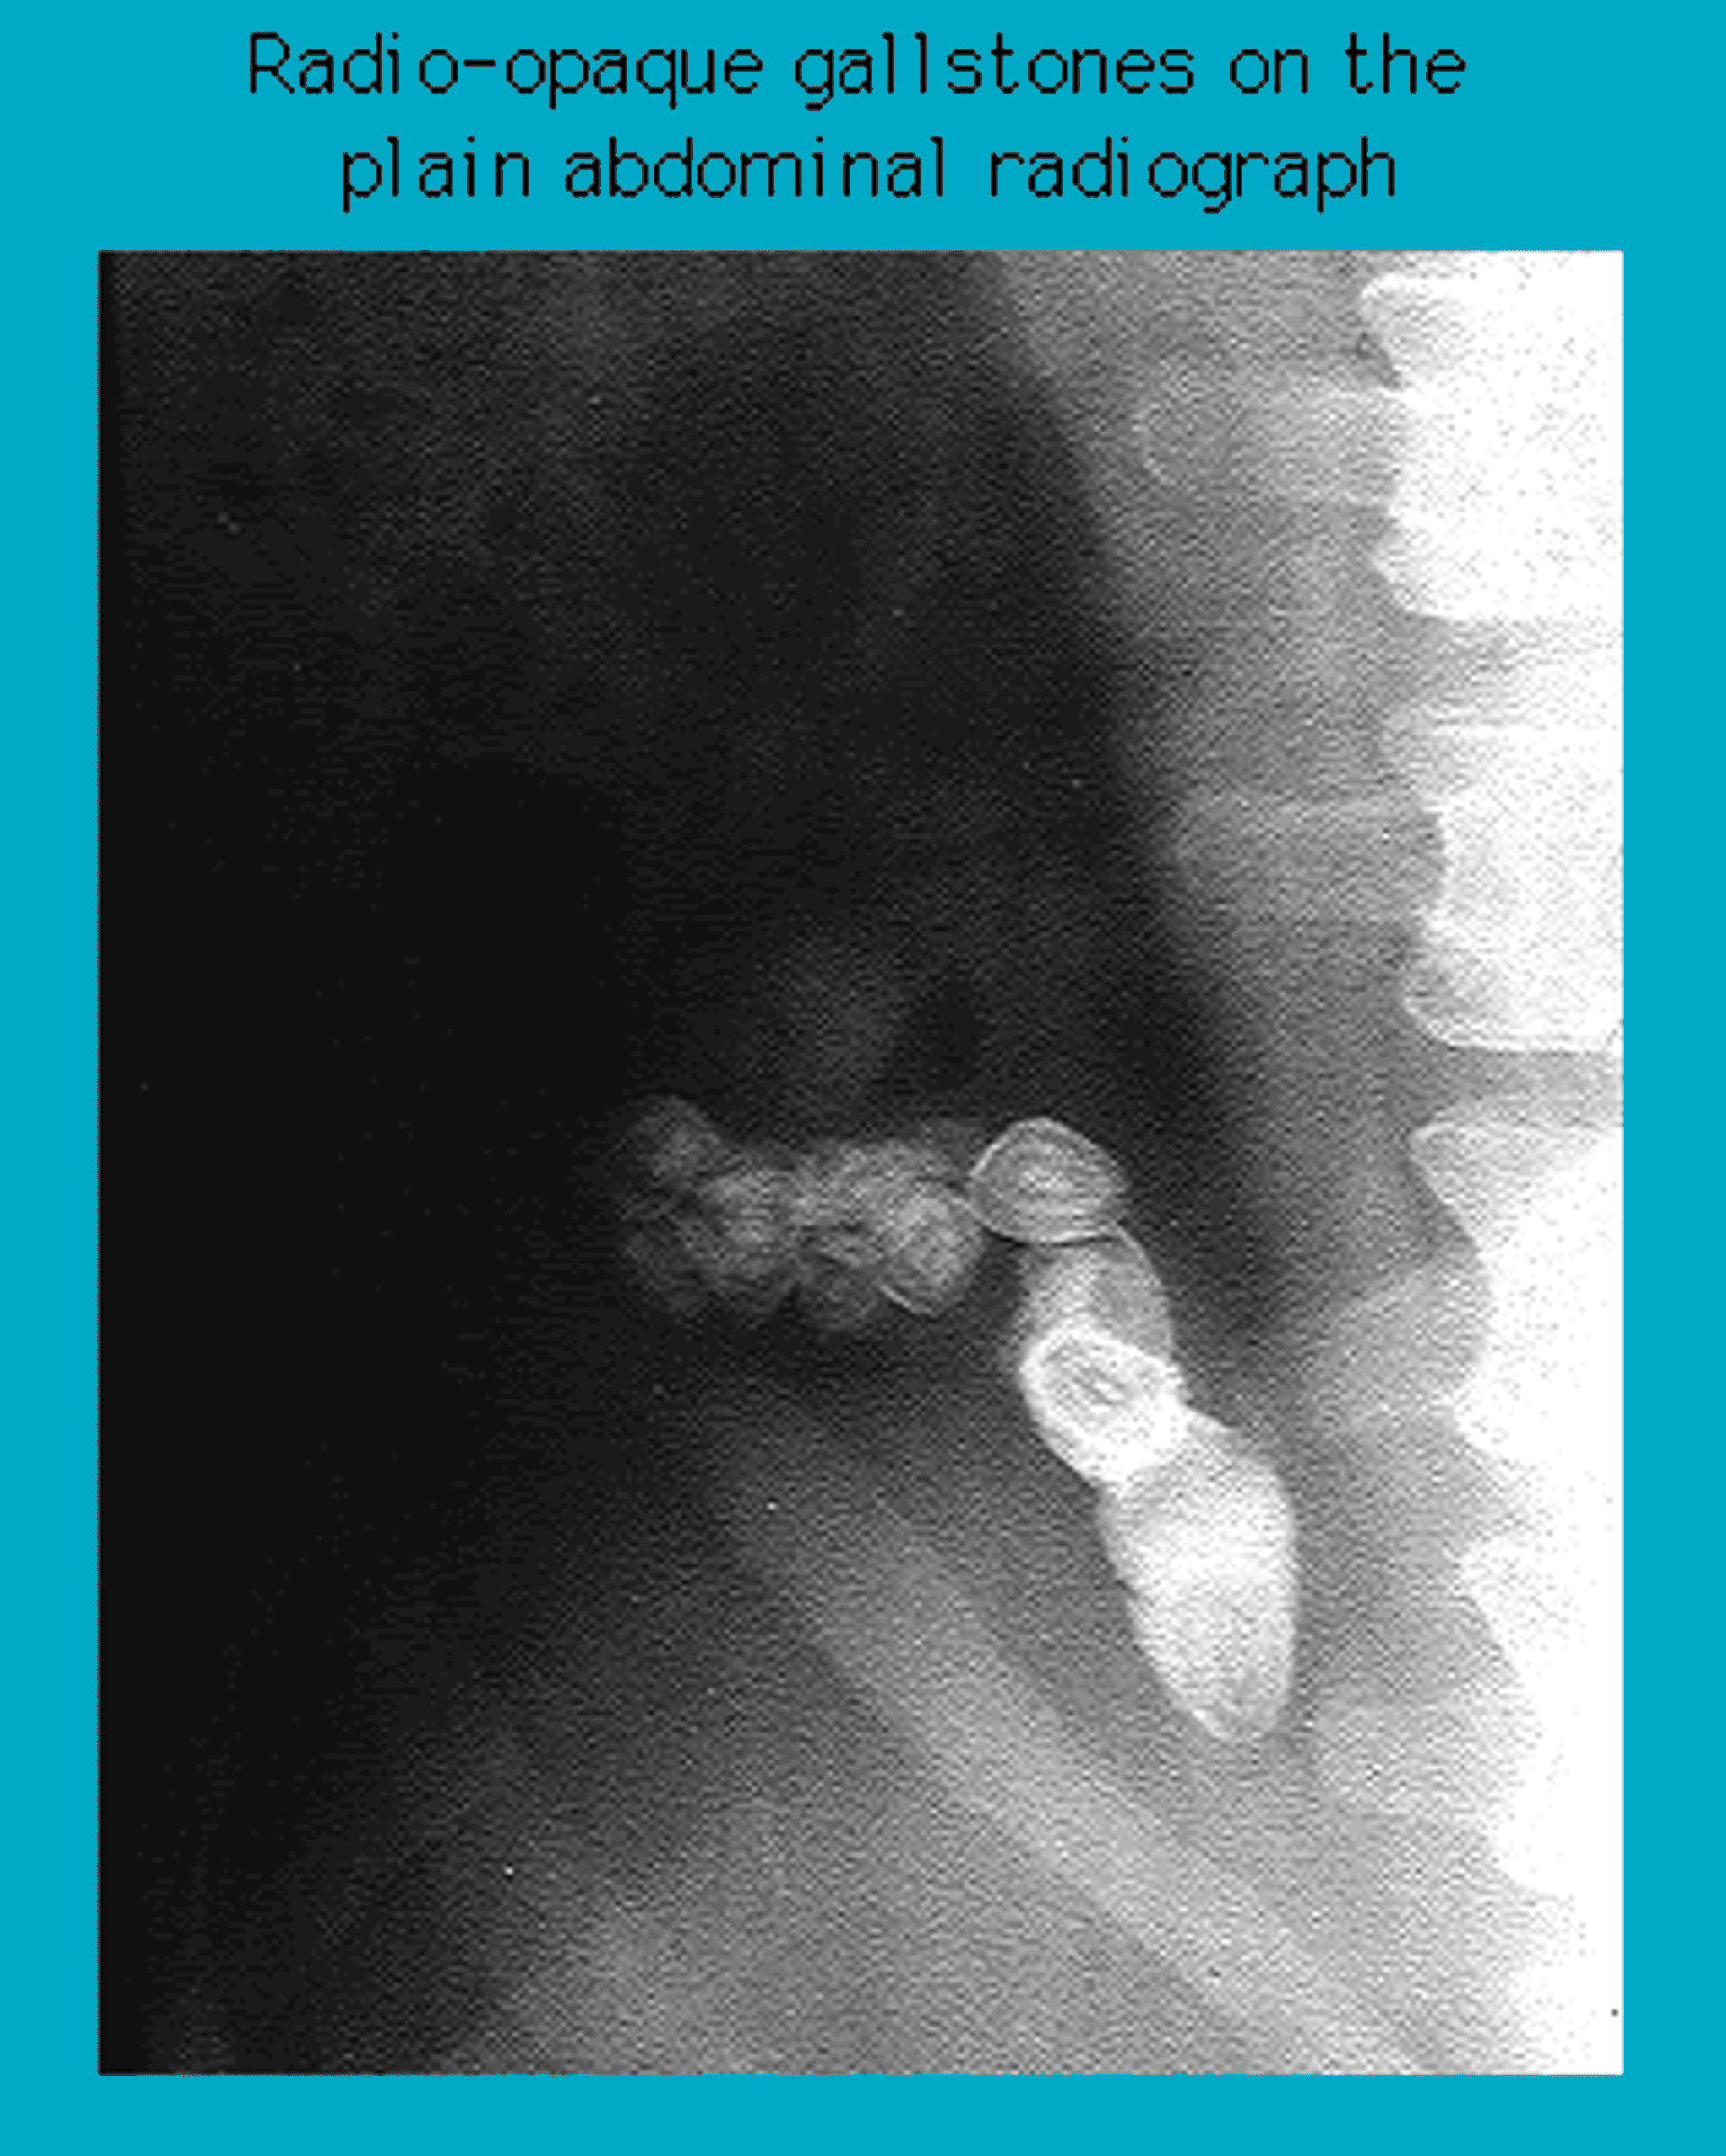

Radiographie montrant des calculs biliaires radio-opaques